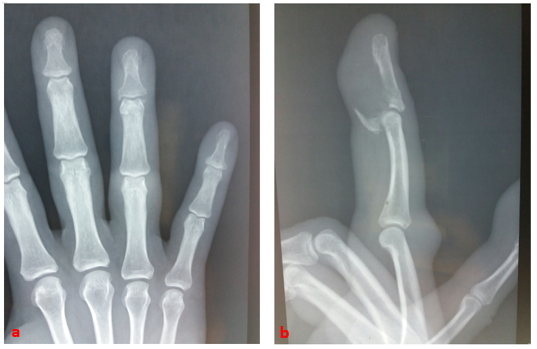

A 49-year-old right-handed police officer suffered a closed trauma to the fourth finger of his left hand as a result of a fall in his height. He then experienced a violent pain concomitant with a cracking sensation, then an impossibility. active flexion of the distal phalanx. The clinical examination, found a finger slightly edematous, ecchymosed. A flexion attitude of the proximal metacarpophalangeal and interphalangeal joints of the same radius, the IPD was in extension and its active flexion impossible (Figure 1). Simple radiographs of the left frontal and lateral annular hands (Figure 2a, b) have led to the diagnosis of anterior marginal articular fracture of the P3 base.

Figure 2a,b Standard radiograph of the front and profile fingers of the annulus confirms fracture tearing of the fragment of the base of the distal phalanx.